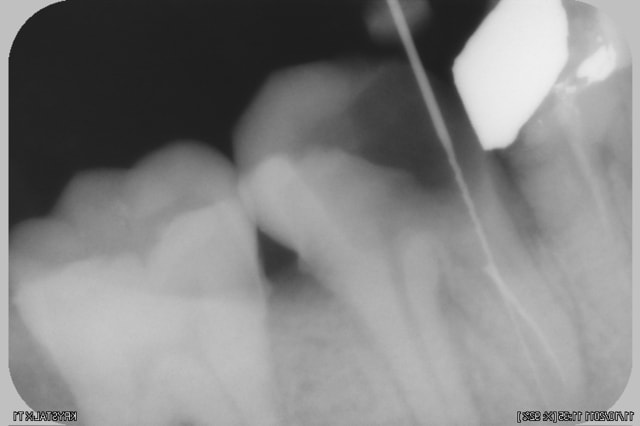

voila une lime cassée qui a engendré un probleme

est ce reparable?? si on va tenter du MTA, comment localiser spatialement la lesion????

Je ne comprends pas pourquoi tu voudrais utiliser du MTA. Sur la première radio on dirait que la limes est en dehors de la racine, le pronostic de la dent ne me parait pas très bon...

evidement MTA pour la reparation de la perfo